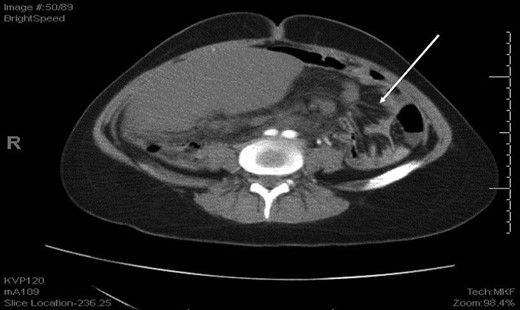

An axial CT of the upper level of the abdomen shows a corkscrew-like soft tissue density (white arrow) indicating twisted splenic vessels surrounded by peritoneal ligaments and fats forming a whirly appearance with alterative lucent and dense bands (a whirl sign), is a pathognomonic CT findings of torsion.

An axial CT shows dilated engorged mesenteric vessels (white arrow) indicating mesenteric varices.